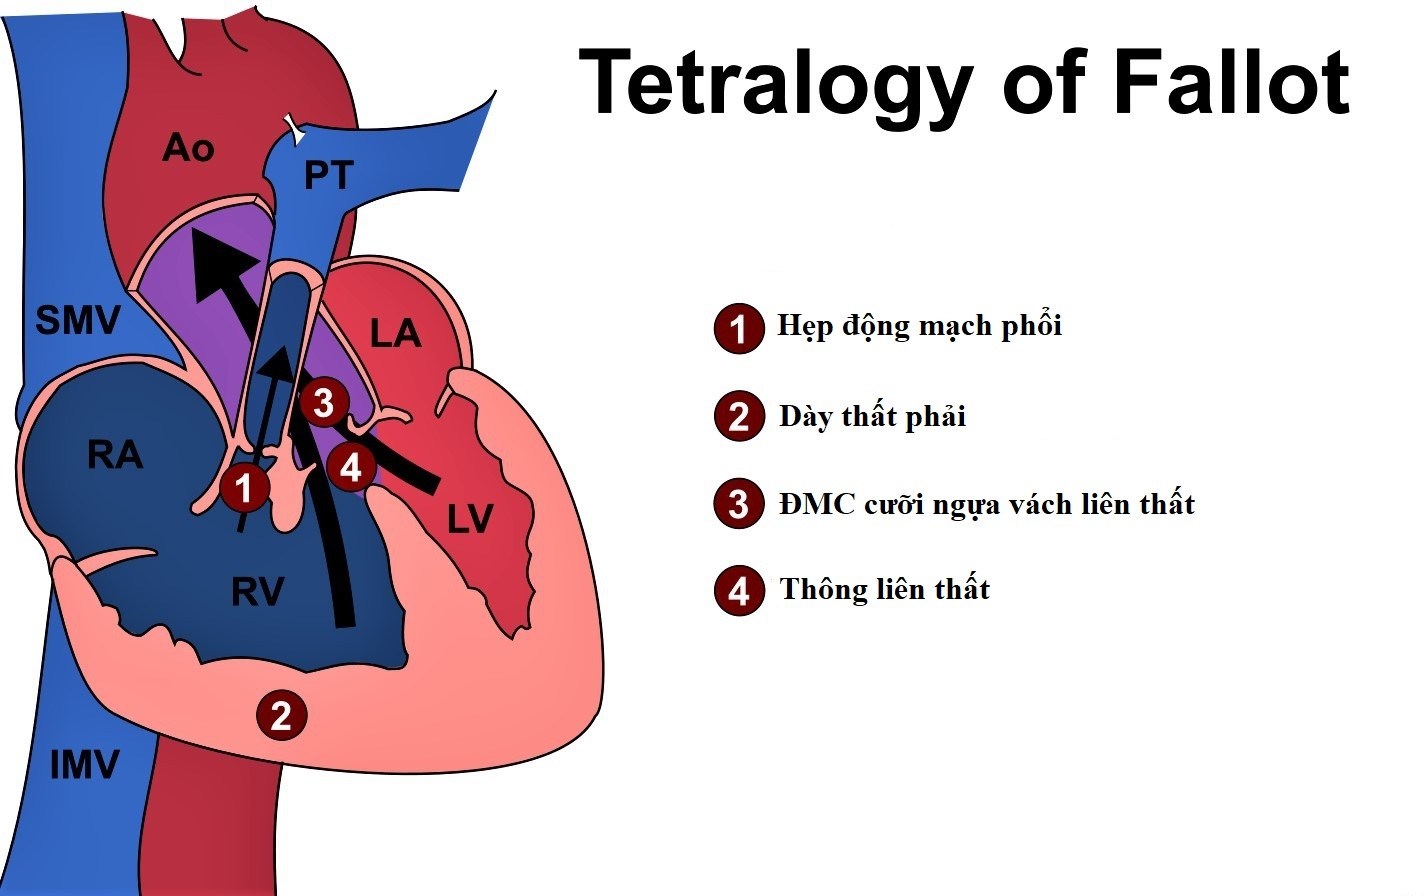

– Bao gồm 4 tổn thương:

+ Thông liên thất: quanh màng, cơ bè

+ Động mạch chủ lệch phải cưỡi ngựa trên vách liên thất

+ Hẹp đường thoát thất phải (hẹp động mạch phổi): hẹp van, hẹp phễu, không lỗ van, không van, hep nhánh xa động mạch phổi.

+ Dày thất phải.

+ Phối hợp: cung động mạch chủ bên phải (25%), còn ống động mạch (2%), bất thường động mạch vành.

– Sinh lý bệnh:

+ Tăng gánh áp lực thất phải: dày thất phải => xơ hóa thất phải => suy tim phải.

+ Shunt phải => trái: tím nặng khi khóc hoặc gắng sức.

– Bóng tim thường không lớn, đôi lúc nhỏ hơn bình thường

– Khuyết cung động mạch phổi (do hẹp động mach)

– Tim hình chiếc giầy (Boot-shaped): thất phải phì đại, mỏm tim chếch lên.

– Tuần hoàn phổi giảm: các động mạch phổi nhỏ => phế trường sáng.

– Quai động mạch chủ thường nằm bên phải (25%)5. Hẹp eo ĐM chủ